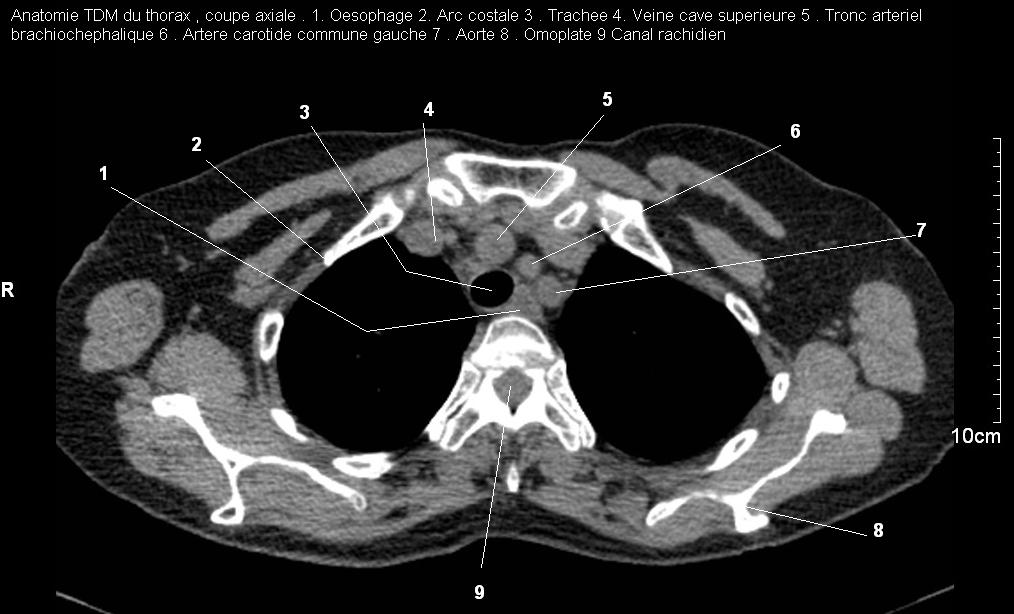

Image TDM normale du mediastin : Sur la TDM image

radiologique de mediastin en voyait très nette , en avant

est le sternum et sa jonction des côtes et en arrière c'est

la colone vertebrale .

Sa contenant est le cœur,

l'œsophage,

la trachée et

les deux bronches souches

, de gros vaisseaux

sanguins et lymphatiques,

ainsi que des nerfs

Imade radiologique TDM normale du

mediastin en coupe axiale à travers apical , et à

travers à supperieur de sinus Valsava de aort

ascendente . Le trache , les deux bronchous ,

vaiseaux de hile , des chaines ganglionaires et des

grands vaisseaux sont en vue et interpreter

facilement .